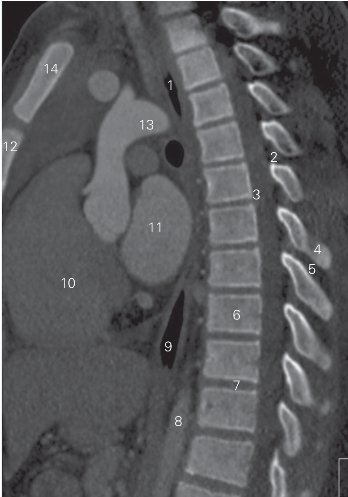

图2-4 经脊柱胸段的正中矢状断层CT图像(骨窗)

1 气管 trachea 2 黄韧带 ligamentum flavum

3 硬膜囊 dural sac 4 棘突 spinous process

5 胸棘间肌 interspinal muscle of thorax

6 第9胸椎椎体 9th thoracic vertebral body

7 第10胸椎间盘 10th thoracic intervertebral disc

8 胸主动脉 thoracic aorta 9 食管 oesophagus

10 左心室 left ventricular 11 左心房 left atrium

12 胸骨体 body of sternum 13 动脉弓 aortic arch

14 胸骨柄 presternum